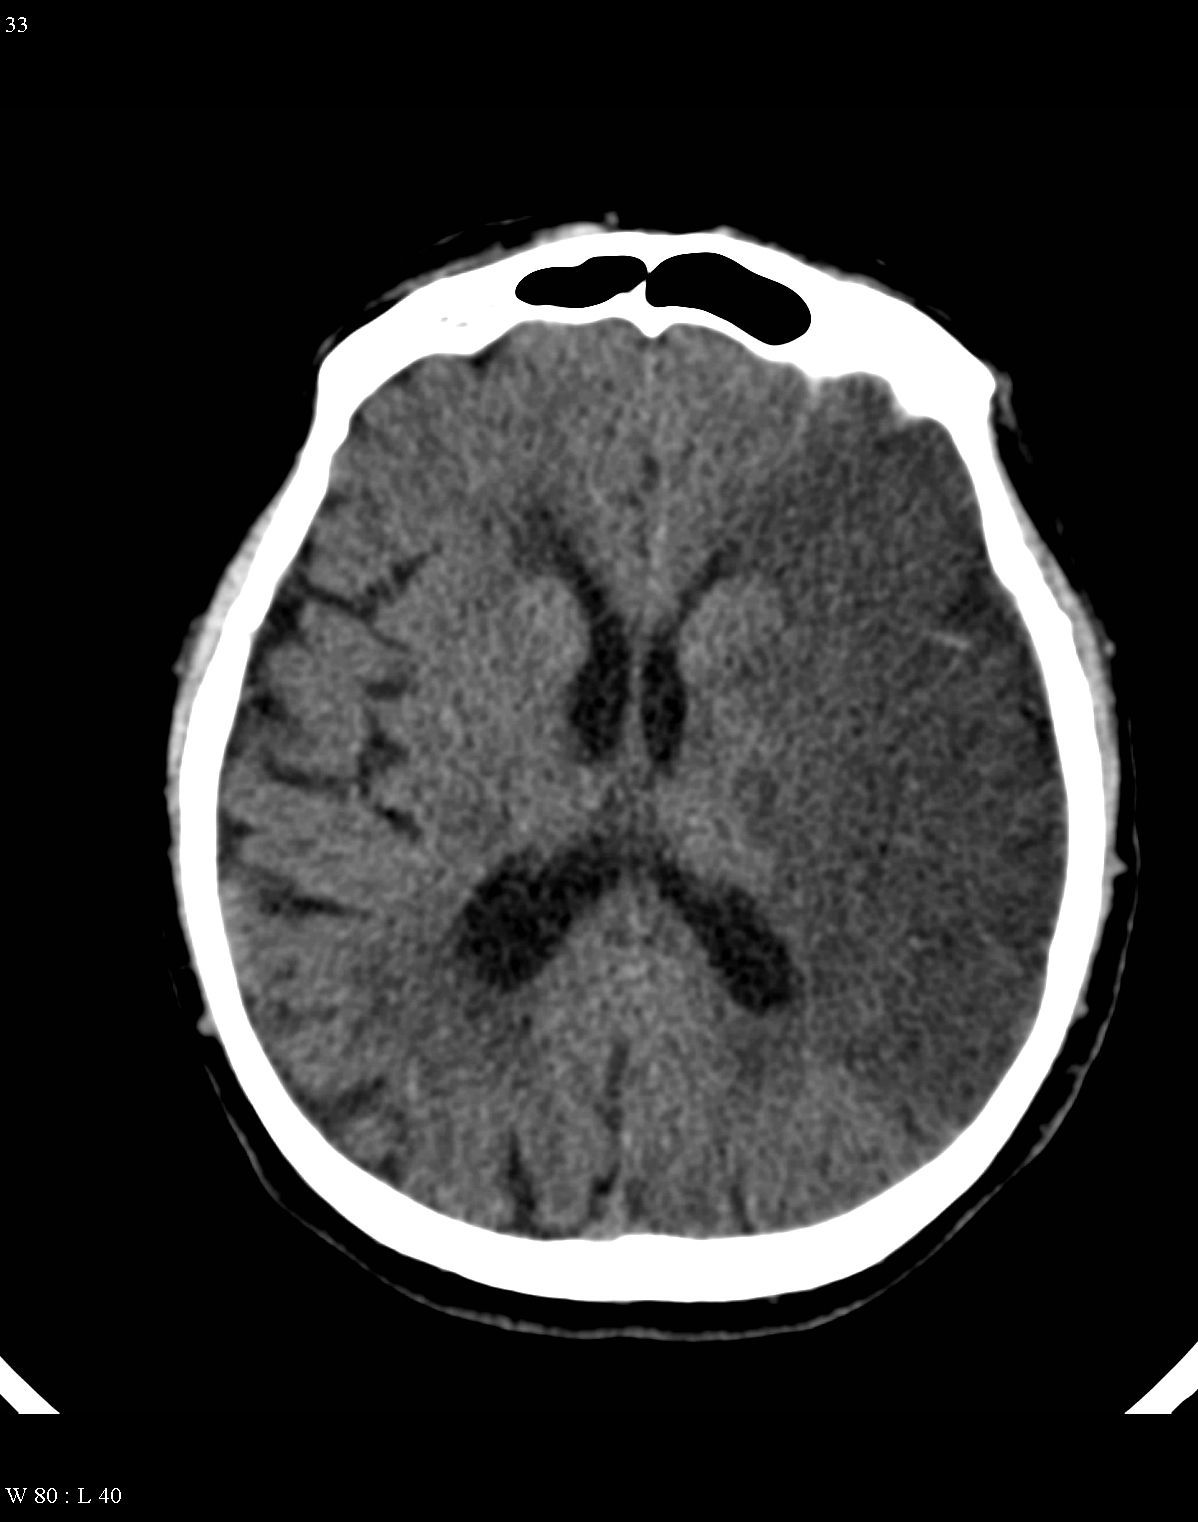

On CT images acute bleeding always presents as hyperdensity. (One has to keep it mind that hyperdensity of the blood is affected by the hematocrit levels, hence making the diagnosis more difficult.) Intraparenchymal blood is dominated by a destructive appearance (mass-effect) and it is surrounded by hypodensity as a sign of perifocal edema. It often breaks into the ventricles. In patients lying in a supine position they collect (sediment) at the occipital horn of the lateral ventricles, creating a hyperdense liquid-to-liquid levels. Later on, the density of blood decreases and shows a peripheral ring or rim-like contrast enhancement without mass-effect.

Although, subarachnoid hemorrhage (SAH) is most often caused by the rupture of a berry aneurysm, arteriovenous malformation (AVM) and trauma can also lead to it. SAH is typically located at the basal subarachnoid spaces, which then propagates along the lateral fissures or it fills up the interhemispheric fissure till the convexities. The main collection of the blood is usually indicative of the source of origin. In cases of parenchymal spread the mechanism, whether it broke in, or it broke out from the parenchyma could represent a differential diagnostic challenge. When accompanied by brain edema, the consequent herniation can result in parenchymal infarcts as well.

CT angiography examination is usually advisory in order to confirm the site of the bleeding. It is also effective when a hemorrhagic tumor is in the differentials, although complete differentiation might only be achieved by follow-up examinations. CTA is also essential in the diagnostics of multiple aneurysms (which are prevalent in 20-30% of the cases based on autopsy reports.) In case of a subarachnoid hemorrhage the consequently developing hydrocephalus and its degree might only be detected on follow-up CT examinations. It is very important to note that an initial brain aneurysm rupture might be followed by a second one within the first 7 – 10 days and the resulting vasospasm carries a much higher risk of mortality than the one at the time of the first SAH. This is why the scrutonius review of the acute diagnostic imaging is essential and it plays a fundamental role in patient treatment. Open brain surgery of the aneurysm (clipping) has been replaced by catheter angiography (DSA) nowadays. The aneurysm is either filled up with thrombogenic coils through its neck or recently bypassing stents are inserted to exclude the aneurysm from the cerebral circulation.